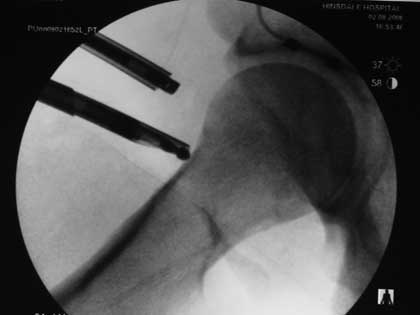

Severe slip treated with arthroscopic Dunn type of femoral neck osteotomy

Severe slip treated with arthroscopic Dunn type of femoral neck osteotomy, reduction and fixation.